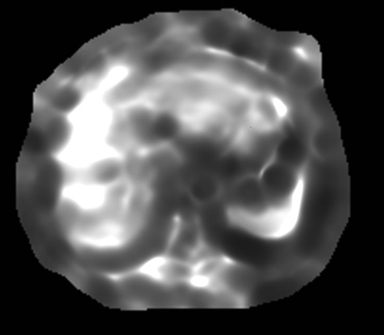

MR-Touch acquisition generates the following image types: magnitude, phase maps, wave maps, and an attenuation map. Six relative stiffness images are reconstructed for each slice location. The relative stiffness images are reconstructed in color and grey scale, and in masked and un-masked versions. Mask portion is depicted as a checkerboard pattern on the image. It is created to identify regions that should not be included in ROI measurements.

Figure 1. Anatomic/Magnitude image

Figure 3. Grey Elastogram, no mask